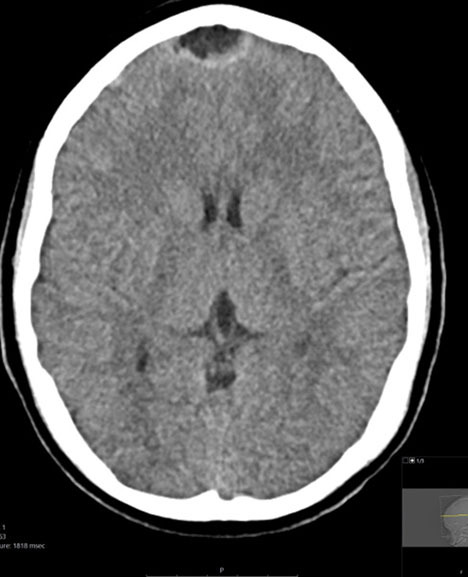

Symptoms typically have an indolent onset, starting with low fevers and headache, and progressing to vomiting and neurologic changes. A head CT or magnetic resonance imaging (MRI) of the brain allows for an accurate diagnosis. See Figures 9 A-B for a brain MRI that depicts the typical findings of abscesses secondary to Streptococcus. Figures 10 A-C show a classic epidural abscess. Given the possibility of elevated intracranial pressure, lumbar puncture should be avoided because of the risk of herniation.

Figure 10A. Epidural Abscess |

![]() |

Axial contrast-enhanced computed tomography of a midline epidural abscess Used with permission from Mark Warren, DO, Dayton Children’s Hospital. |

Figure 10B. Epidural Abscess |

Sagittal contrast-enhanced computed tomography of a midline epidural abscess Used with permission from Mark Warren, DO, Dayton Children’s Hospital. |

Figure 10C. Epidural Abscess |

Diffusion-weighted magnetic resonance imaging of midline epidural abscess Used with permission from Mark Warren, DO, Dayton Children’s Hospital. |